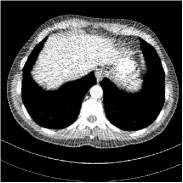

This special case of SUPER corresponds to the case where SUPER excludes the unsupervised regularizer, while only involves the data-fidelity and a supervised regularizer in the MBIR cost, i.e., β=0𝛽0\beta=0 and μ0𝜇0\mu\neq 0. In this case, the proposed SUPER model is similar to a generalized block coordinate descent-based network by replacing a simple denoising autoencoder [28, 29, 30] with a general CNN that forms our supervised regularizer. This SUPER is also similar to the plug-and-play ADMM-Net method except that the inputs to each supervised network are the preceding reconstructions, while plug-and-play ADMM-Net updates inputs to the network (denoiser) based on auxiliary variables in the ADMM algorithm. Here, we used μ=1×106𝜇1superscript106\mu=1\times 10^{6}, which worked well for the plug-and-play ADMM-Net method, for this special case of SUPER. Fig. 7 shows a comparison between plug-and-play ADMM-Net, SUPER without unsupervised regularizers (in both training and testing), and the full SUPER version with ULTRA regularization (β=5×103𝛽5superscript103\beta=5\times 10^{3}, μ=5×105𝜇5superscript105\mu=5\times 10^{5}). All these methods used WavResNet as their denoisers/supervised networks. In this example, SUPER with only a supervised regularizer (SUPER-WRN-β=0𝛽0\beta=0) outperforms the plug-and-play ADMM-Net (ADMM-Net (WRN)) by 1.6 HU RMSE and provides sharper image details. Comparing SUPER-WRN-β=0𝛽0\beta=0 and the full SUPER-WRN-ULTRA scheme, we observe that the latter provides a lower RMSE and higher contrast image features than the former that excludes the unsupervised component. This again shows the effect of the unsupervised ULTRA model (in capturing local image details better with a union of learned transforms) in the SUPER scheme.

Refer to captionADMM-Net (WRN)RMSE = 32.90 HURefer to captionADMM-Net (WRN)RMSE = 32.90 HU

Refer to captionSUPER-WRN-β=0𝛽0\beta=0RMSE = 31.32 HURefer to captionSUPER-WRN-β=0𝛽0\beta=0RMSE = 31.32 HU

Refer to caption SUPER-WRN-ULTRARMSE = 29.74 HURefer to caption SUPER-WRN-ULTRARMSE = 29.74 HU

Refer to caption ReferenceRefer to caption Reference

Figure 7: Reconstructed images of L192 slice 150 with WavResNet plugged ADMM-Net, SUPER-WRN-β=0𝛽0\beta=0 (both training and testing), and SUPER-WRN-ULTRA (β=5×103𝛽5superscript103\beta=5\times 10^{3} in both training and testing), respectively, shown with the reference image.